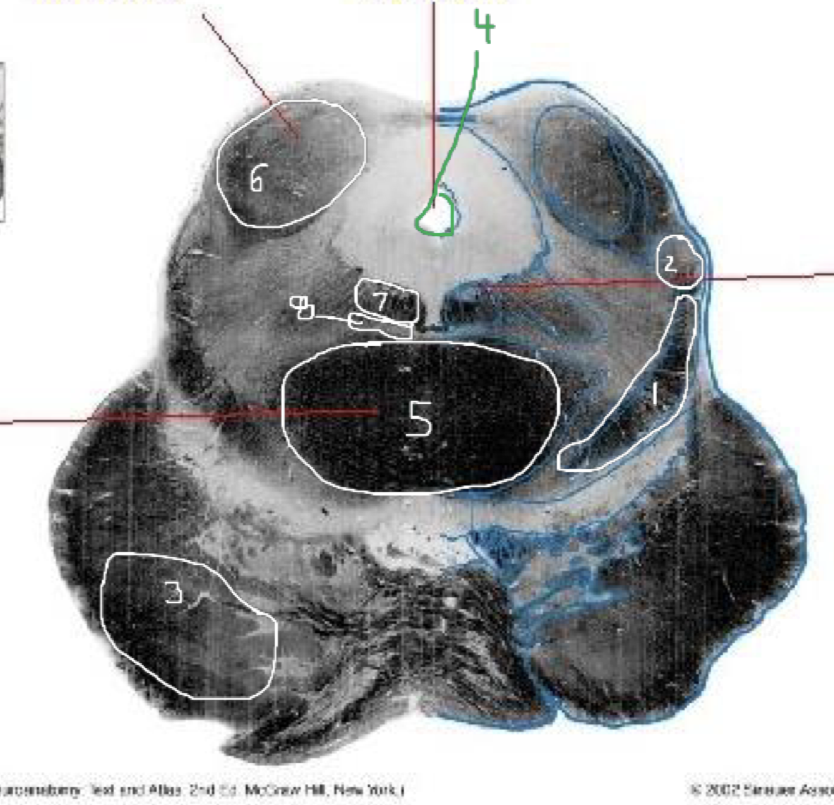

1

Medial Lemniscus - Caudal Midbrain

2

Spinothalamic Tract - Caudal Midbrain

3

CST - Caudal Midbrain

4

Cerebral Aqueduct - Caudal Midbrain

5

Superior Cerebellar Peduncle (Decussation) - Caudal Midbrain

6

Inferior Colliculus - Caudal Midbrain

7

Trochlear Nucleus (CN IV) - Caudal Midbrain

8

Medial Longitudinal Fasciculus (MLF) - Caudal Midbrain